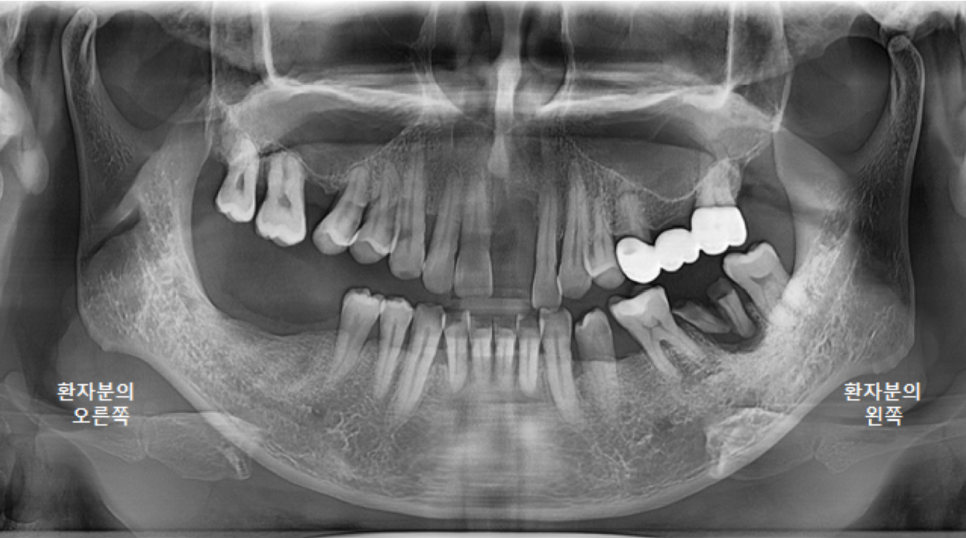

전체적인 구강 판단을 위해

파노라마 엑스레이 사진을 찍었습니다.

왼쪽 큰앞니도 빠져있지만,

오른쪽위 큰어금니, 오른쪽 아래 큰어금니도 발치된 상태였고,

왼쪽 위 브릿지 상태도 좋지는 않았습니다.

왼쪽 아래 큰어금니 하나는 뿌리만 남은 상태였어요.